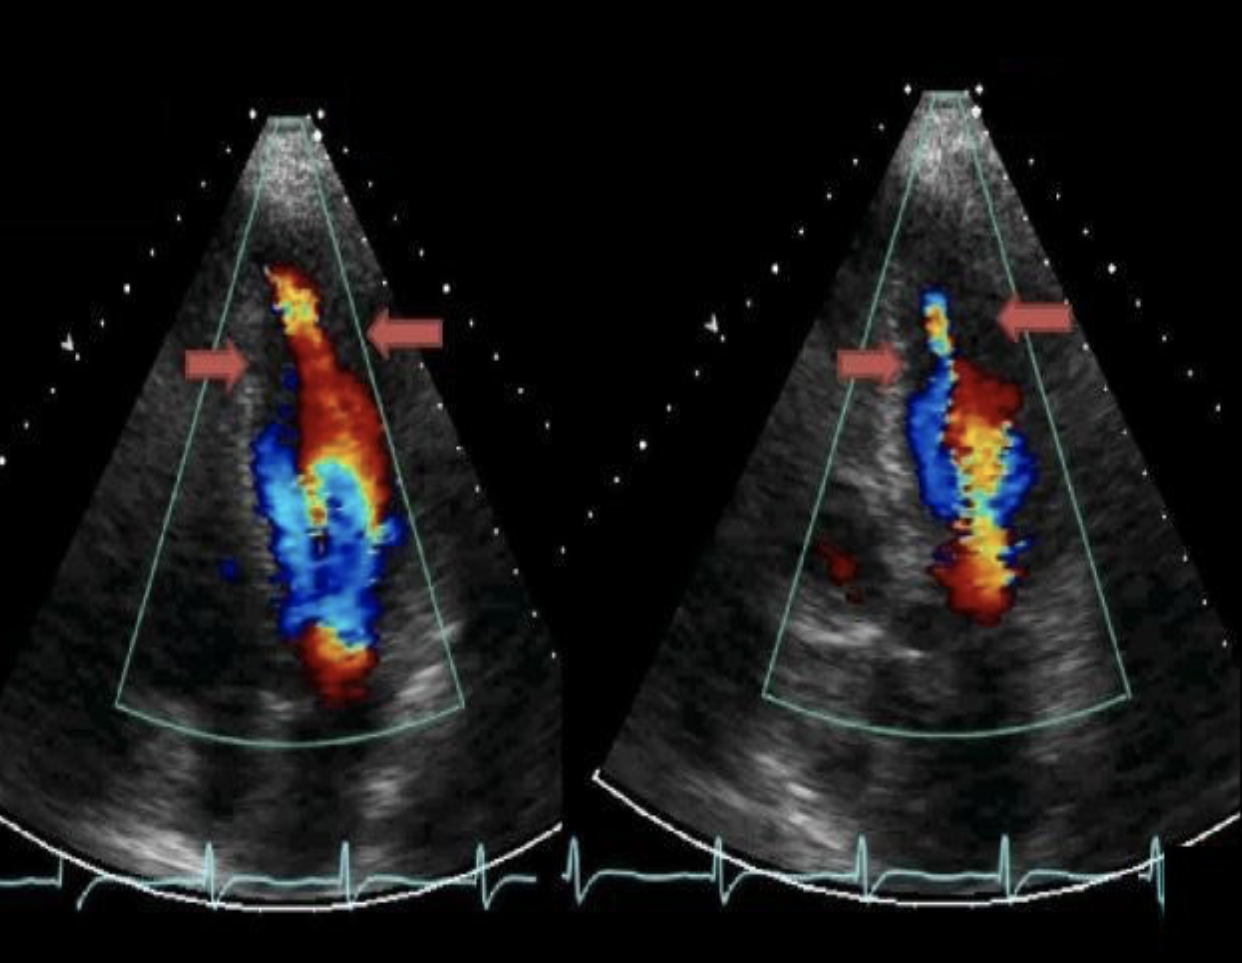

Which left heart abnormality will cause the aortic CW Doppler flow pattern demonstrated in the image?

HCM

Which of the following valvular abnormalities is commonly associated with the abnormality on the image?

SAM